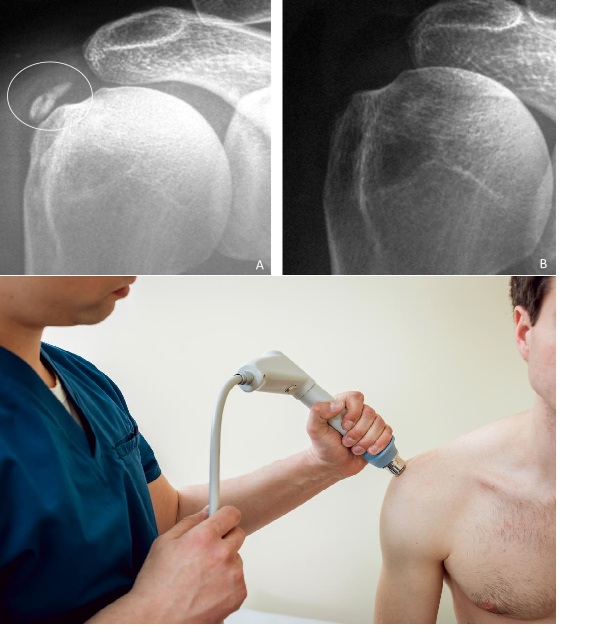

3.2 Phân loại X-quang theo Gärtner & Heyer

Phân loại này dựa trên hình thái học trên X-quang và tương quan với giai đoạn bệnh học. Đây là công cụ tiên lượng quan trọng trong lựa chọn điều trị:

LoạiHình thái X-quangCấu trúc vôiGiai đoạn tương ứngTiên lượng

Type I Đậm đặc, đồng nhất, bờ rõ (dense, homogeneous) Canxi dạng hạt thô – rắn chắc (formative) Pha tạo thành / nghỉ Khó hút qua kim; ưu tiên ESWT

Type II Không thể phân loại rõ ràng vào I hoặc III Trung gian Chuyển tiếp Đáp ứng biến thiên

Type III Mờ, không đồng nhất, bờ không rõ (fluffy, translucent) Canxi dạng huyền phù sữa – lỏng (resorptive) Pha tiêu hủy Dễ hút qua kim; barbotage hiệu quả cao

Ý nghĩa lâm sàng: Gärtner Type I (rắn) → kết quả hút kém, ưu tiên ESWT hoặc phẫu thuật. Gärtner Type III (lỏng) → dễ hút qua barbotage, hiệu quả cao nhất khi đau cấp tính.

🖼 Hình 4 – Phân loại Gärtner trên X-quang

Type I: bờ đậm rõ | Type II: trung gian | Type III: mờ, bờ không rõ

Phân loại Gärtner trên X-quang

5.3 Sóng Xung Kích Ngoài Cơ Thể (ESWT)

⚡ Chỉ định ESWT

• Thất bại điều trị bảo tồn sau 6–12 tuần

• Gärtner Type I hoặc II (vôi rắn – barbotage khó hiệu quả)

• Kích thước nốt vôi 1–3 cm

• Giai đoạn mạn tính (chronic calcific stage)

• Không trong giai đoạn tiêu hủy cấp tính nặng

• ESWT năng lượng cao được khuyến cáo mạnh (high-energy focused ESWT)

Chống chỉ định ESWT: Rối loạn đông máu, thai kỳ, implant kim loại vùng điều trị, nhiễm trùng tại chỗ.

Phác đồ điển hình: 3 buổi, cách nhau 1–2 tuần; 2.000–3.000 xung/buổi; năng lượng 0,20–0,40 mJ/mm².

Meta-analysis và systematic review đều xác nhận ESWT năng lượng cao cải thiện điểm Constant-Murley đáng kể sau 12 tháng, với tỷ lệ tiêu vôi hoàn toàn/một phần đạt 60–80%.

🖼 Hình 8 – ESWT: X-quang trước và sau 3 buổi điều trị

Trái: Gärtner Type II trước ESWT. Phải: thoái lui đáng kể sau điều trị

ESWT X-quang trước và sau điều trị